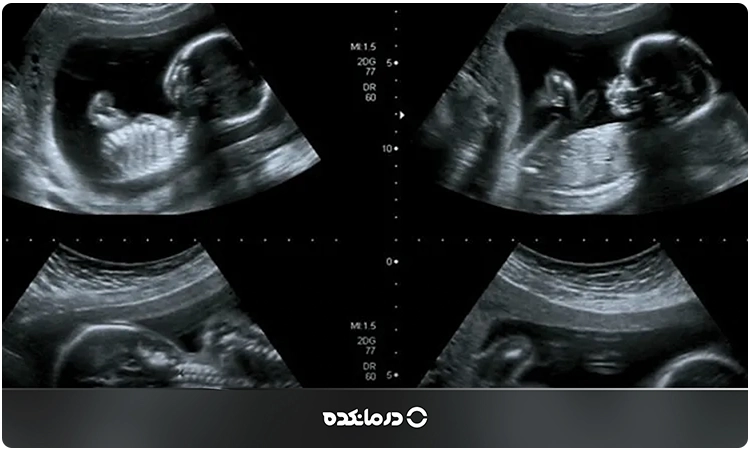

در این بررسی، سونوگرافیست معمولا از سونوگرافی دو بعدی برای مشاهده اندامهای جنین استفاده میکند، اما در برخی موارد ممکن است برای وضوح بیشتر از تصاویر سه بعدی یا چهار بعدی نیز کمک بگیرد.

سونوگرافی آنومالی چگونه انجام میشود؟

پزشک سونوگرافی از شما میخواهد به پشت روی تخت دراز بکشید، درست مانند انجام سونوگرافی شکم و لگن. احتمالا به شما میگوید کمی به سمت پهلوی راست یا چپ بچرخید تا هم تصویر واضحتری از جنین بگیرد و هم جریان خون رحم بهتر برقرار بماند.

سپس ژل را روی سطح شکم میمالد تا تماس بین پوست و دستگاه بهتر برقرار شود و امواج صوتی راحتتر عبور کنند. در مرحله بعد پروب (همان وسیله دستی سونوگرافی) را روی شکم حرکت میدهد تا وضعیت شکم و جنین را به صورت تصویر سیاه و سفید روی مانیتور ببیند.

در طول اسکن پزشک به اندامهای جنین، ستون فقرات، قلب، شکم، جفت، بند ناف و میزان مایع آمنیوتیک نگاه میکند و اندازهگیریهای مهمی انجام میدهد. مثلا دور سر، دور شکم، طول استخوان ران و رشد جنین باید با سن بارداری مطابقت داشته باشد.

سونوگرافی معمولا ۲۰ تا ۴۵ دقیقه طول میکشد، اما اگر وضعیت جنین پیچیده باشد یا نیاز به بررسی دقیق قلب باشد ممکن است کمی بیشتر طول بکشد.